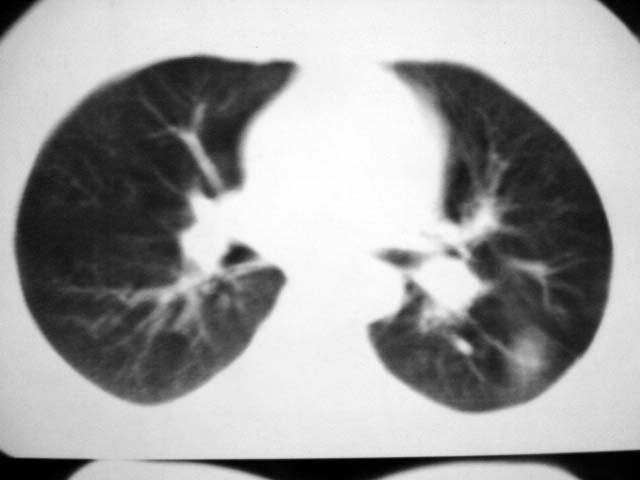

标题: CT12463:女,19岁,炎性假瘤?结核球? [打印本页]

女,19岁,体检时发现。炎性假瘤?结核球?

考虑右肺炎性假瘤或球形肺炎,建议抗炎治疗后复查。

球形肺炎或炎性假瘤。

考虑球形肺炎。